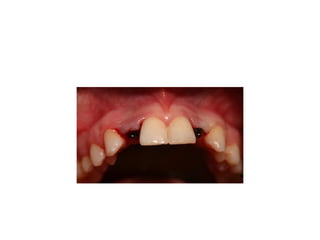

time of insertion

retainer has been modified

final crowns are delivered